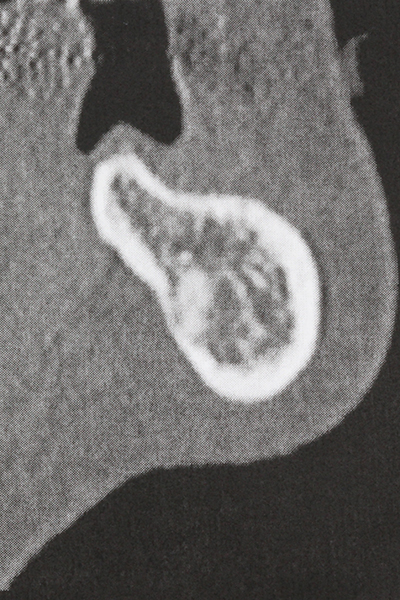

Фиг. 17a: CT изображение на стимулиращата растеж остеотомия в непосредствена близост до...

Фиг. 17b: алвеоларния канал с нервни окончания (латерален и коронарен изглед).